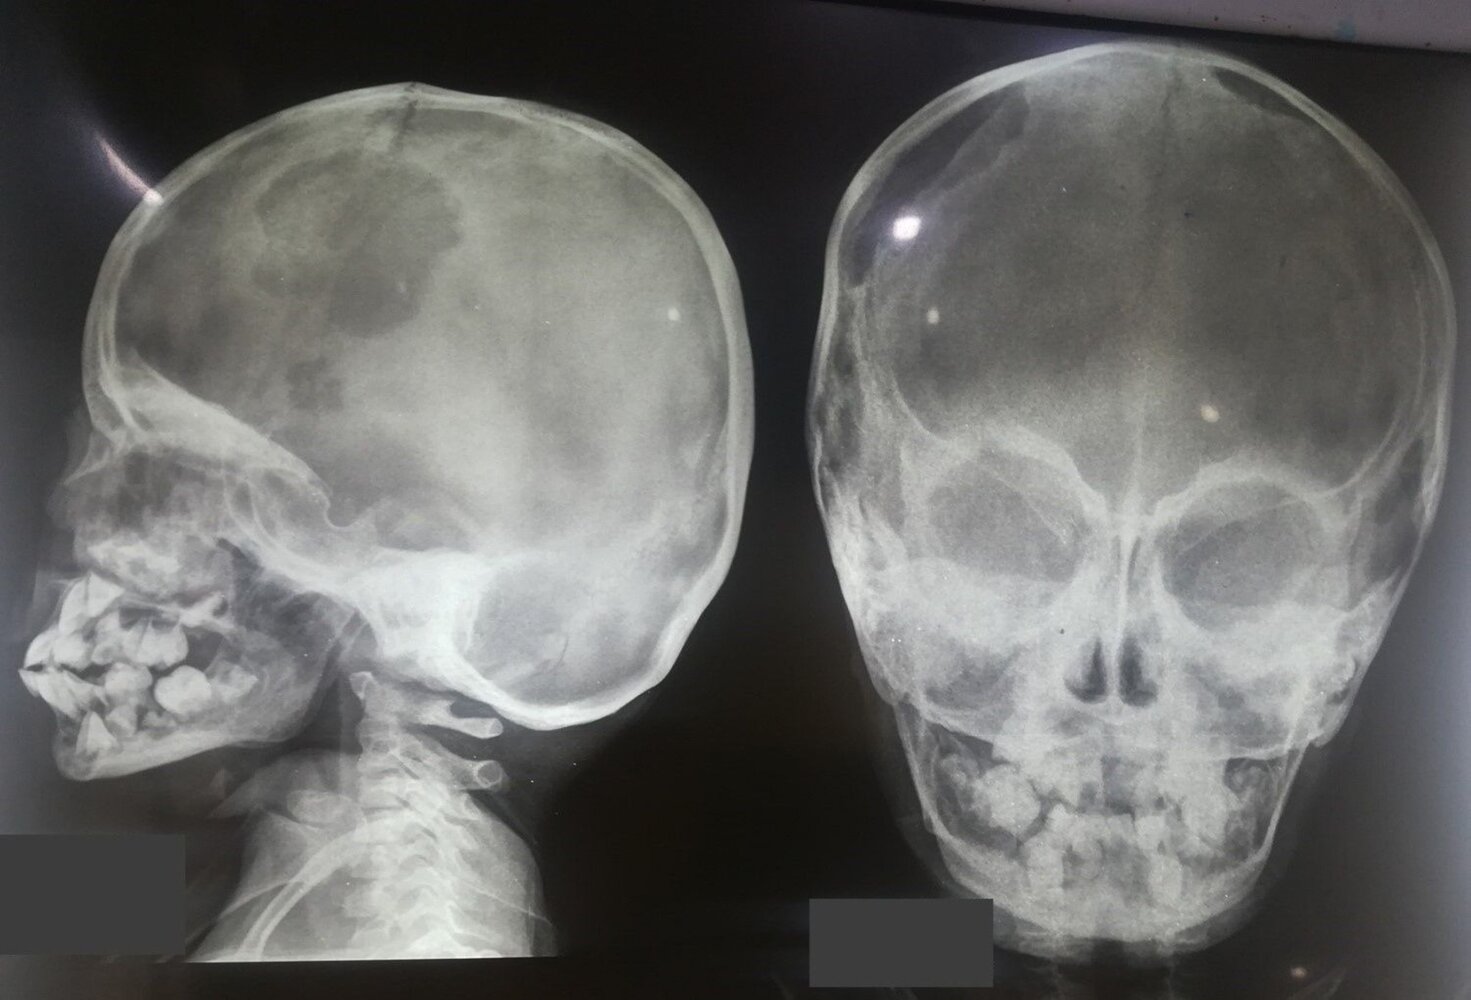

• Lytic lesion consisting of Langerhans and immune cells

• Peak incidence: 5–10 years

• Most commonly in the skull

• Painful swelling

• Pathologic fracture

• X-ray: osteolytic lesions with or without marginal sclerosis

• Typically, solitary lesions

• May manifest with rash and recurrent otitis media with mastoid swelling

• Lesions near the sphenoid, orbital, ethmoid, or temporal bones require treatment with vinblastine and prednisone.

• Description: : a rare disorder caused by clonal proliferation of Langerhans cells (antigen-presenting cells) [11]

• Epidemiology: : peak incidence between 5 and 10 years

• Clinical features

• Osseous lesions (90%): pain and/or swelling, pathological fractures

• Localization: skull (most common site), femur, vertebra, mandible, ilium, ribs

• Can cause recurrent otitis media if the mastoid bone is involved

• Unifocal or multifocal

• Diagnostics